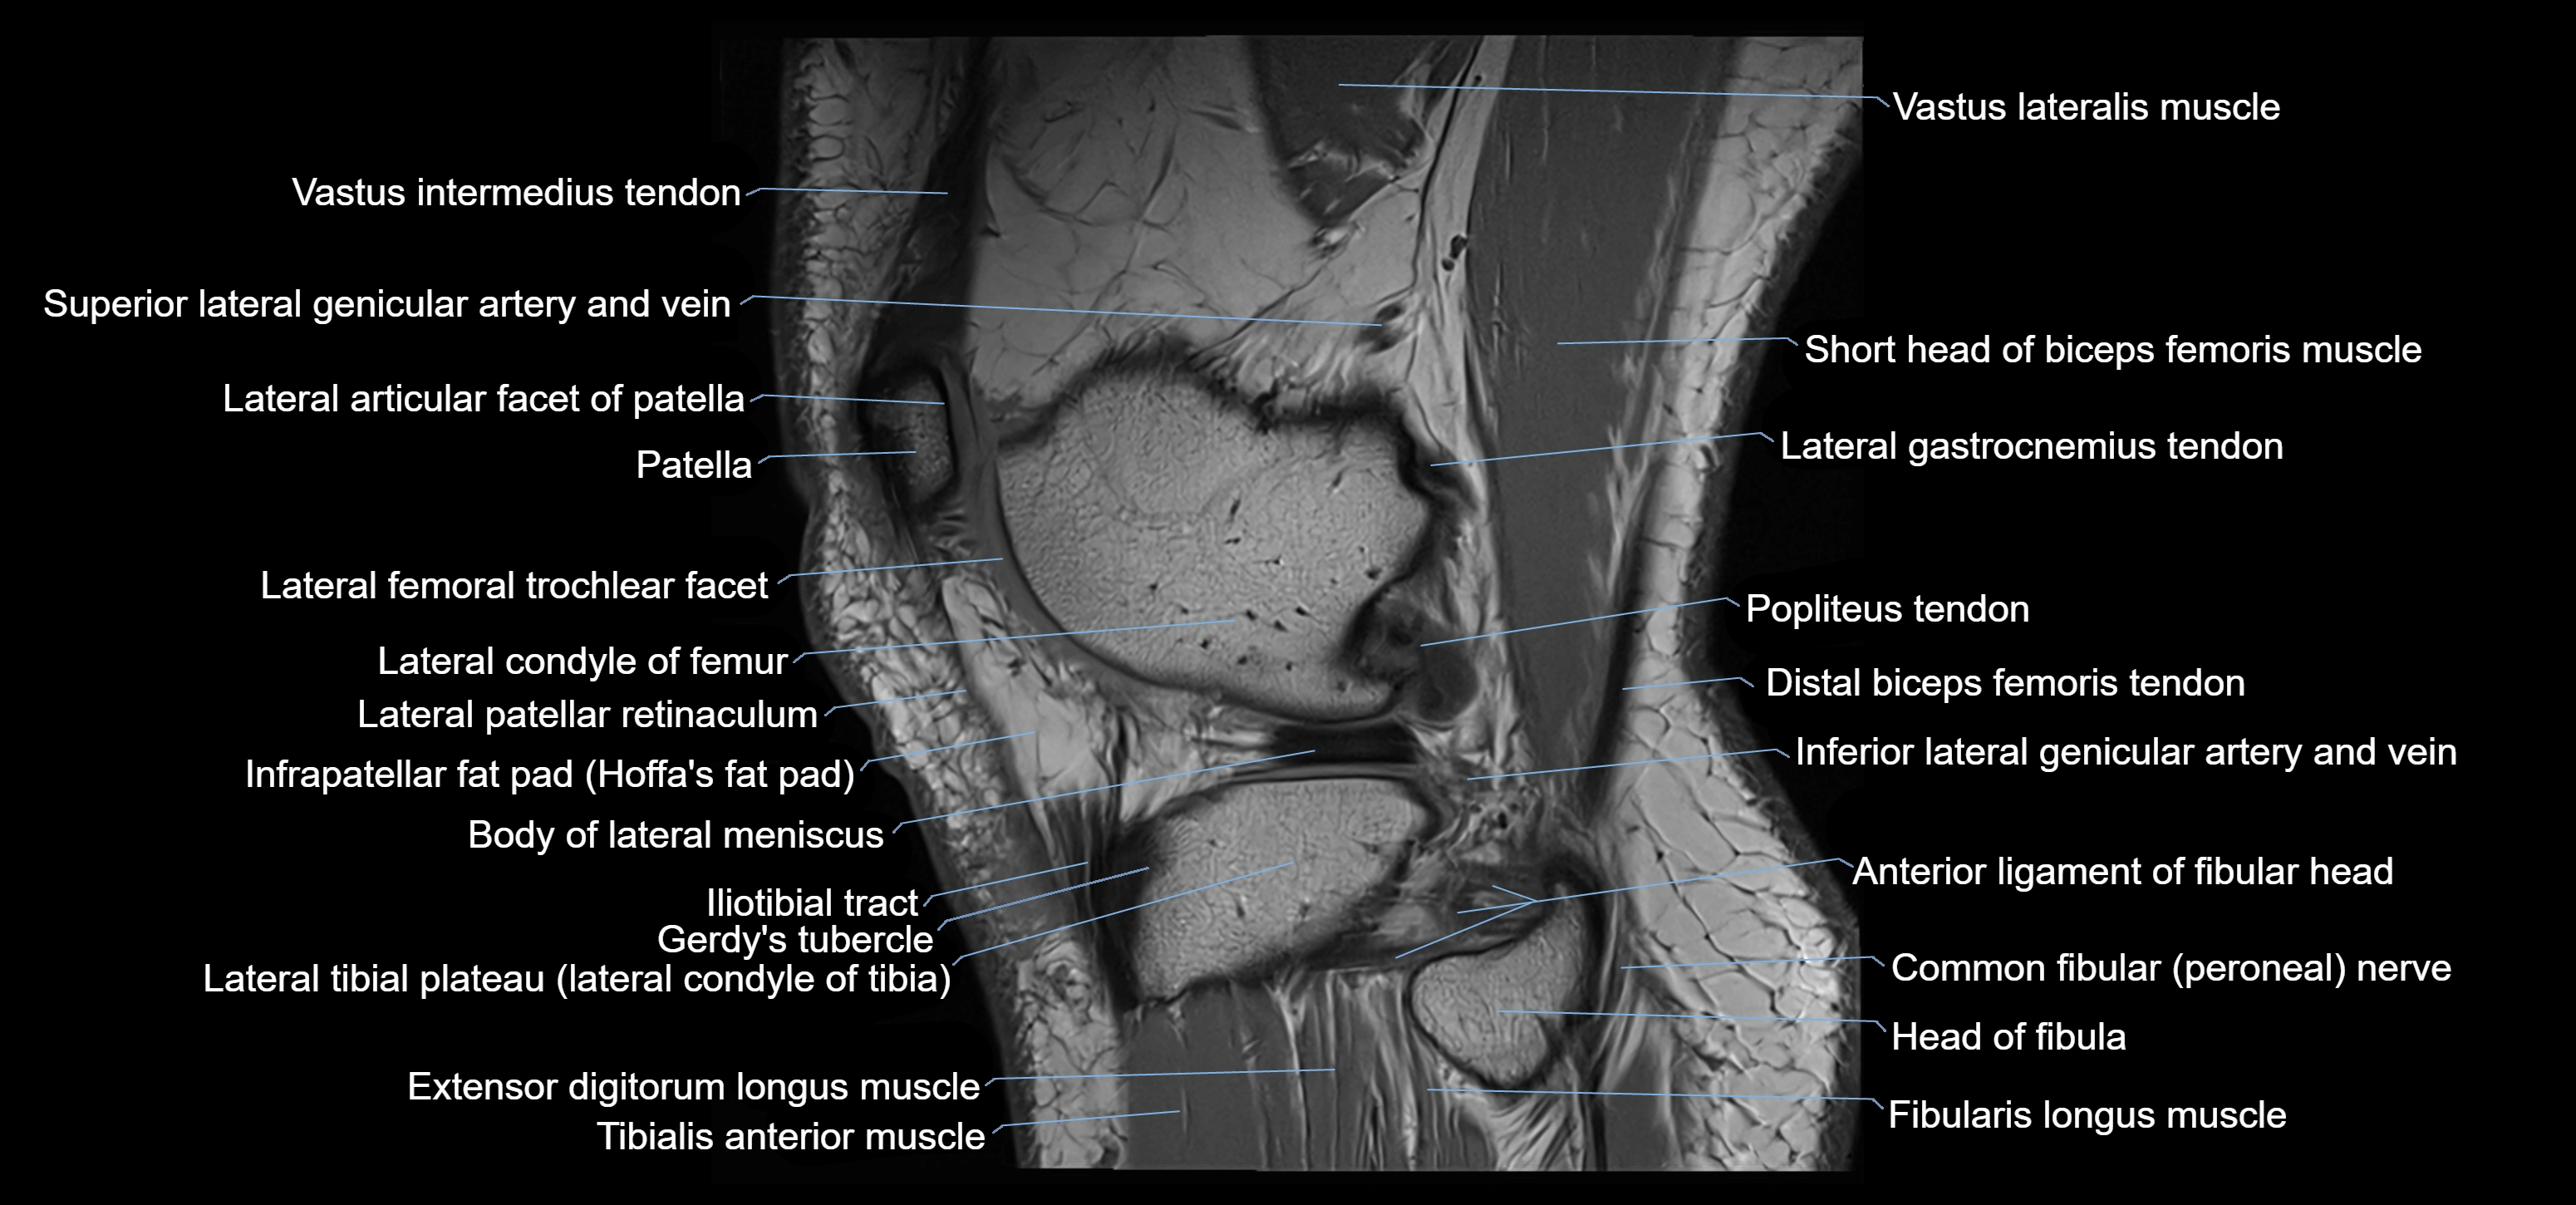

- Body of lateral meniscus

- Extensor digitorum longus muscle

- Fibularis longus muscle (peroneus longus muscle)

- Gerdy’s tubercle

- Head of fibula

- Lateral articular facet of patella

- Lateral condyle of femur

- Lateral gastrocnemius tendon

- Lateral head of gastrocnemius muscle

- Lateral patellar retinaculum

- Lateral tibial plateau

- Patella

- Popliteus tendon

- Superior lateral genicular artery

- Superior lateral genicular vein